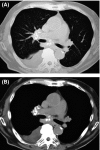

A 77-year-old man was referred to our hospital due to enlarging mediastinal/hilar lymphadenopathy with calcification. Endobronchial ultrasound-guided transbronchial needle aspiration (EBUS-TBNA) and bone marrow aspiration were performed. Subsequently, monoclonal gammopathy of undetermined significance (MGUS) associated with mediastinal amyloidosis was diagnosed. We hereby report a case in which EBUS-TBNA led to a successful diagnosis of amyloidosis.